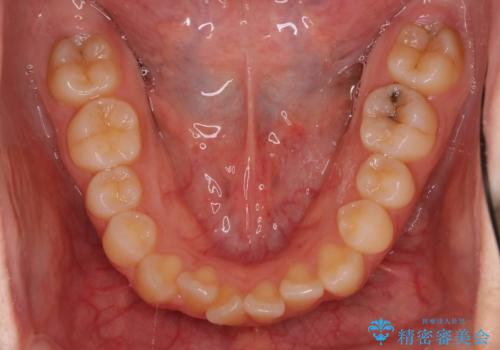

インビザラインによるガタつきの矯正治療 シンプル・短期間

- 非抜歯、IPR+拡大によるマウスピース矯正を計画した。

一見前歯のガタつきだけのように見えても、そのガタつきの根本的な原因が奥歯の位置であったりすると、マウスピースの枚数がそれなりに多くなり、治療に時間がかかることもあります。